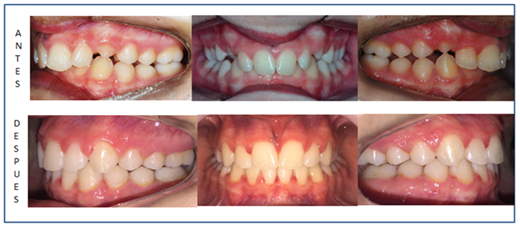

Clinical case performed by Dr. Marcelo Mochó at the orthodontic clinic (Figure 9 & 10).

Patient 14 years old. In this case, the twin blocks were cemented, as the patient was rebellious to the continuous use of the appliance. In the aesthetic study it is highlighted: diminished lower third and protruding chin.

In the study of the smile, it is observed: discontinuous staggered smile line (lateral sector in eruption), does not coincide with the curvature of the lower lip. It also interposes the lower lip between the upper and lower incisors.

In the initial intraoral photographs we observe in a frontal view: permanent dentition, severe incisor overbite, physiological underocclusion of teeth 13 and 23, dental midlines coincide.

In the sagittal plane it stands out: Right and Left Class II molar key,

Canine key: It is not registered by physiological underocclusion 13 and 23 but if we can project a Class II. The overjet is increased. Looking at the intraoral photographs at the end of the treatment, we see the effectiveness of the twin blocks and that the achievements were significantly favorable. Let us not forget that in this case the blocks were cemented. The treatment was 1 year and 5 months. Orthodontics was also placed to correct rotations and settle the occlusion. In the study of the profile radiograph (Figure 11) we conclude that the patient is a severe brachyfacial. Her facial convexity is + 1.3mm so it is in the norm, this is due to the fact that the facial plane is used as a reference (it is supported by distant structures: B.C.A / Symphysis) of our "dentoalveolar skeletal field", these can suffer positional and/or morphological variations as in this case, of a very prominent pogonion that masks a Class II.